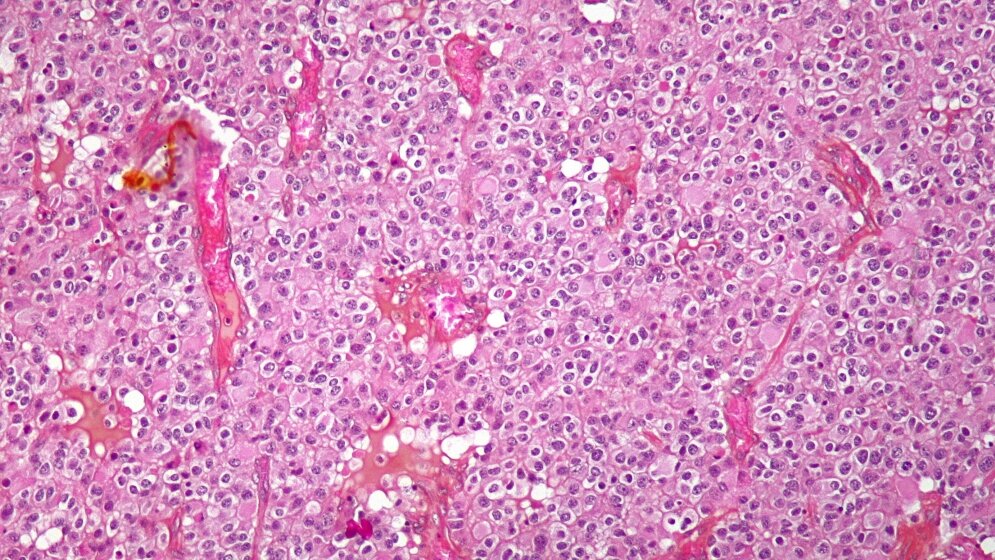

Für die Studie, die jetzt veröffentlicht wurde, hatten Jan C. Buckner von der Mayo Clinic in Rochester und seine Kollegen die Daten von 251 Patienten ausgewertet, die an einem prinzipiell prognostisch günstigen Gliom der Stufe II gemäß Klassifikation der Weltgesundheitsorganisation (WHO) litten. Ein Teil dieser Patienten war unter 40 Jahre alt und hatte eine ungünstigere Prognose, weil ihre Hirntumoren in einer Operation nicht vollständig hatten entfernt werden können. Die restlichen Studienteilnehmer dagegen hatten unabhängig vom Ausgang der Operation alleine durch ihr Alter von über 40 Jahren eine ungünstigere Prognose.